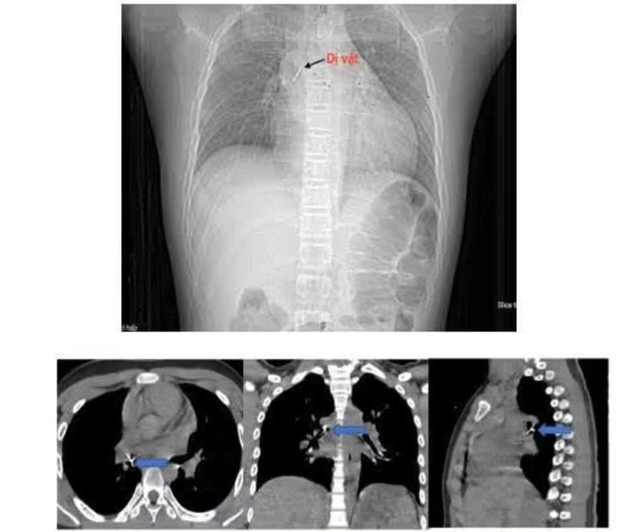

Ngay lập tức, gia đình đưa bé tới bệnh viện gần nhà. Sau chẩn đoán bằng chụp cắt lớp vi tính lồng ngực và nội soi phế quản ống mềm, các bác sĩ xác định dị vật nằm sâu tại phế quản trung gian bên phải, đầu ghim đã đâm xuyên vào thành phế quản gây chảy máu và phù nề.

Sau hơn hai giờ can thiệp tại cơ sở ban đầu không thành công, bệnh nhi được chuyển khẩn cấp tới Bệnh viện Phổi Trung ương. Tiếp nhận ca bệnh, ThS.BSCKII Nguyễn Lê Nhật Minh - Trưởng khoa Nội soi chẩn đoán và can thiệp cùng ê-kíp đã tiến hành nội soi phế quản ống mềm để gắp dị vật.

Theo bác sĩ Minh, dị vật là chiếc đinh ghim sắc nhọn, đầu ghim cắm sâu vào thành phế quản, thao tác lấy rất khó bởi bệnh nhi có phản xạ ho, cần thao tác nhanh, chính xác để tránh làm rách thành phế quản hoặc đẩy dị vật xuống sâu hơn, có thể gây nhiễm trùng, tràn khí màng phổi hoặc suy hô hấp cấp.